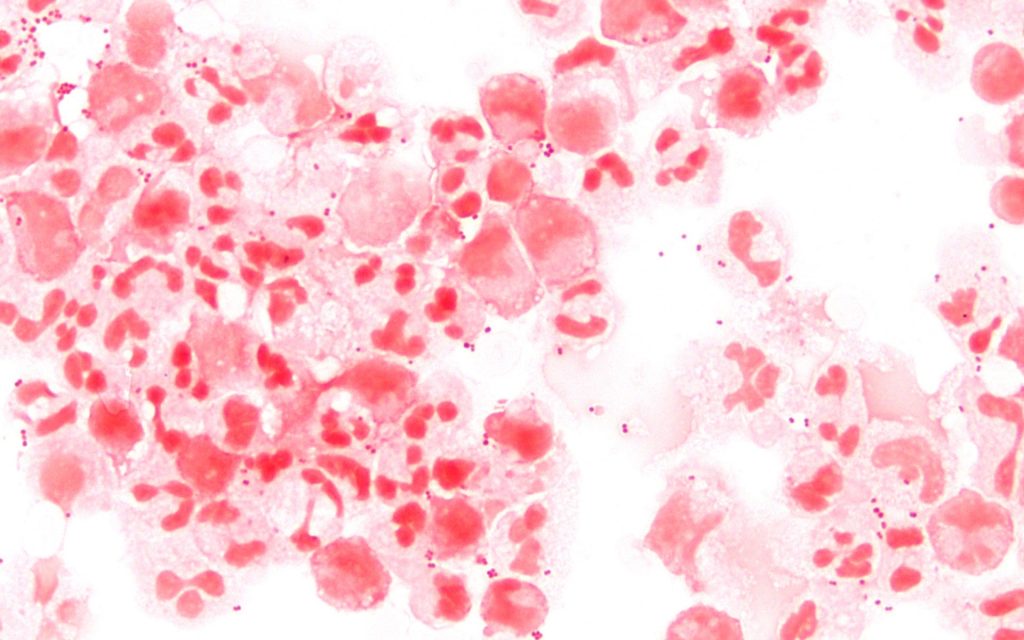

Neisseria meningitidis, a bactéria que causa a meningite meningocócica.

Wikimedia